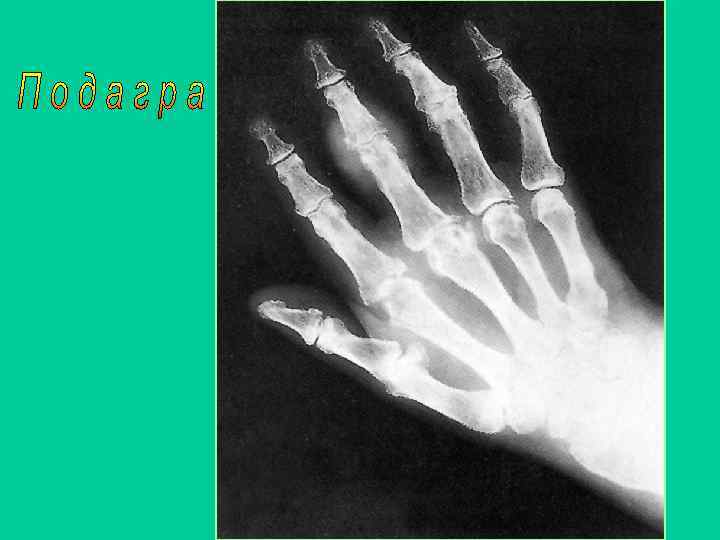

Дополнительные методы обследования • Рентгенография 1 плюснефалангового сустава и кистей • Содержание мочевой кислоты (0, 36 - 0, 42 ммоль/л) • Поляризационная микроскопия